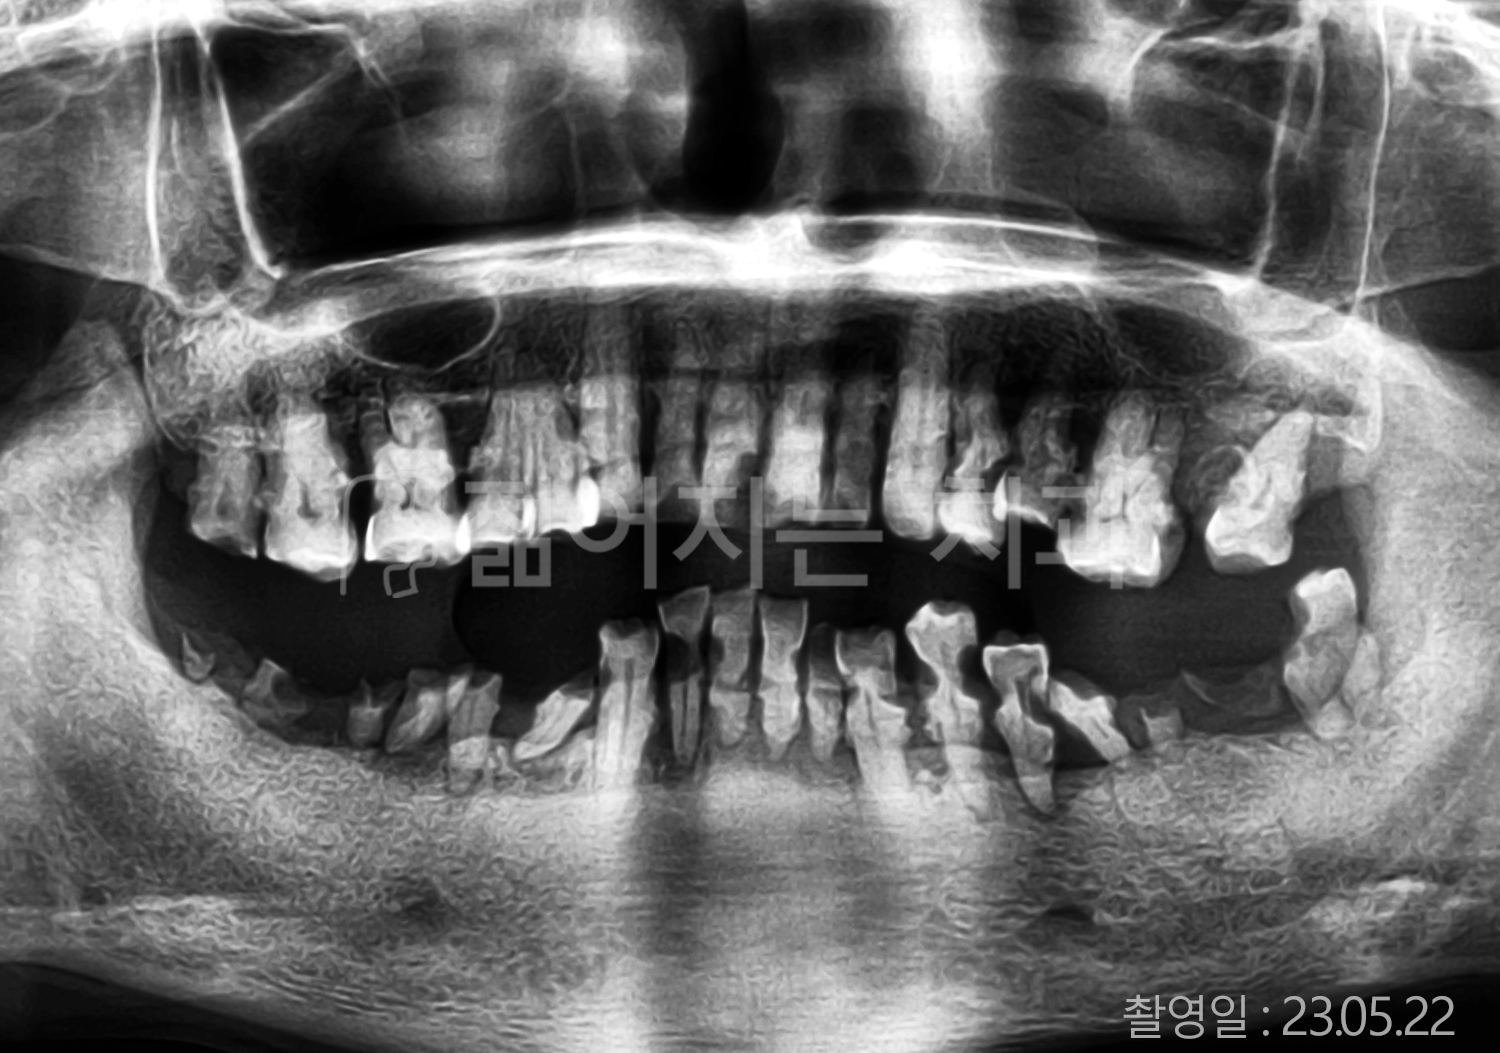

• 70대 고혈압, 당뇨 전체치아 10개 이상 임플란트

• 50대 고혈압, 당뇨 전체치아 10개 이상 임플란트

• 60대 고혈압, 당뇨 전체치아 10개 이상 임플란트

• 50대 전체치아 10개 이상 임플란트

• 70대 당뇨 전체치아 10개 이상 임플란트

• 80대 전체치아 10개 이상 임플란트

• 40대 전체치아 10개 이상 임플란트

• 60대 고협압, 고지혈증 전체치아 10개 이상 임플란트

• 60대 전체치아 10개 이상 임플란트